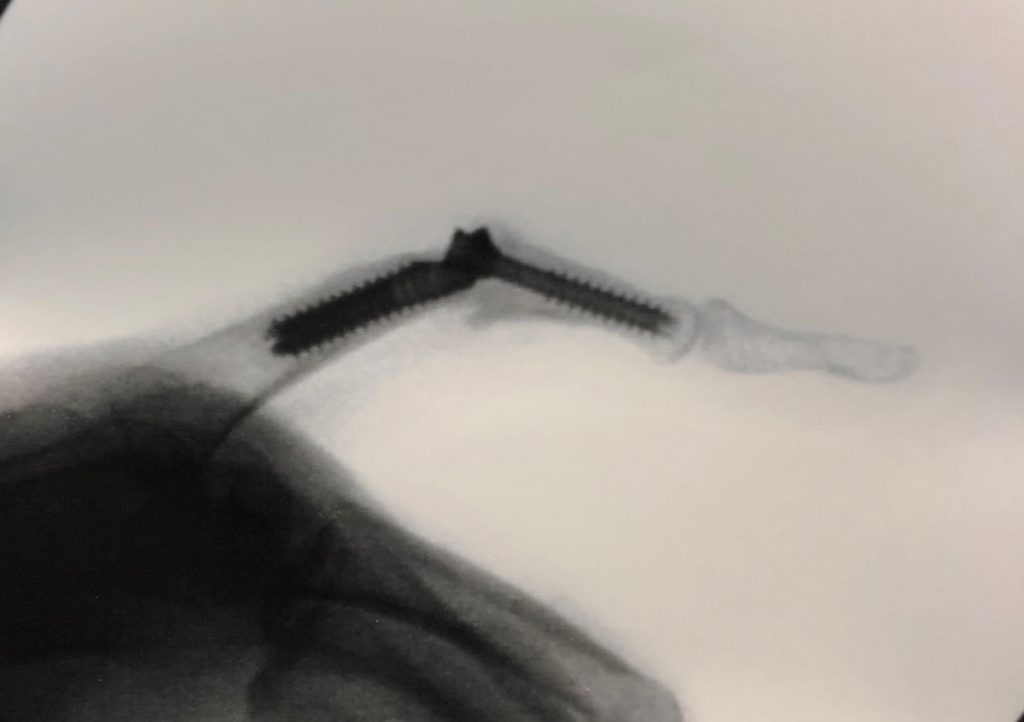

PATOLOGIAS MUÑECA - PRÓTESIS ARTICULARES Figura 3 - Radiografía de Prótesis total de Articulación Radio-Cubital distal

Figura 3 - Radiografía de Prótesis total de Articulación Radio-Cubital distal